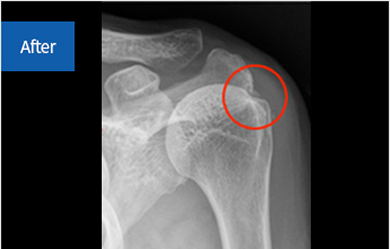

석회제거술이란?

퇴행성 변화로 인해 어깨 힘줄 세포가 괴사하면서 그 조직에 석회질이 침착하게 됩니다.

이로 인해 발생하는 질환인 석회성 건염의 치료 방법 중 하나가

석회성 물질을 제거하고 염증 부위를 절제하는 ‘석회제거술’입니다.

석회화건염

어깨의 회전근개(힘줄) 주변에 석회 물질이 생성되어 극심한 통증을 유발하는 질환을 말합니다.

주로 40~50대 이후 여성에게서 발생하며, 이는 어깨 힘줄의 퇴행성 변화와 관련이 있습니다.

발병 기전은 명확하지 않으며, 복합적 요인으로 인해 발생하는 것으로 추정됩니다.

침착된 석회가 치료 후 없어진 모습

before img after img